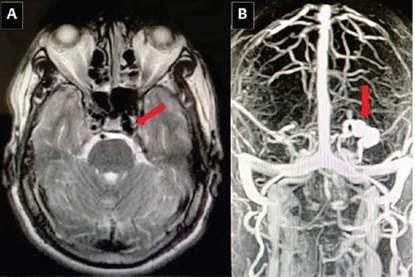

Figura 3 A : resonancia magnética cerebral simple, secuencia T2: dilatación vena oftálmica superior izquierda. B: angioresonancia cerebral fase venosa: dilatación de la vena oftálmica superior izquierda y arterialización de la señal de esta y del seno cavernoso izquierdo.

Al examen físico de ingreso presentó signos vitales con tensión arterial 153/101 mmHg (dados los anteriores registros de tensión arterial del paciente y la intensidad del dolor, se asumió como respuesta ante el dolor), frecuencia cardiaca 53 latidos por minuto, frecuencia respiratoria 20 respiraciones por minuto, temperatura 36,5 °C, SaO2 96 %, proptosis ocular pulsátil y edema palpebral izquierdos (Figura 2A), oftalmoparesia completa bilateral, alerta, consciente, orientado en las tres esferas, pupilas normoreactivas, fuerza y sensibilidad de todos los miembros conservadas, reflejos osteotendinosos ++/++++. Su cuadro no respondió a diferentes medidas analgésicas instauradas como dipirona 1 gramo IV cada 6 horas, tramadol 50 mg IV cada 8 horas, hidromorfona 0,3 mg IV cada 4 horas, y al siguiente día después de su ingreso empezó a presentar aumento del edema, la proptosis ocular se hizo más notoria y se presentó disminución más marcada de su agudeza visual bilateral medida por tabla de Snellen (20/100 ojo derecho (OD) 20/200 ojo izquierdo (OI)). De este modo, ante el antecedente de TCE leve, cefalea con banderas rojas, alteraciones visuales, oftalmoparesia, proptosis pulsátil en ojo izquierdo y alteración de la agudeza visual, se decidió descartar trombosis del seno cavernoso versus FCC, por lo que se solicitó en primera instancia IRM cerebral simple, donde se encontró dilatación de la vena oftálmica superior izquierda (Figura 3A), que se complementó con angioresonancia cerebral que confirmó dilatación de 18 mm de la vena oftálmica superior izquierda con arterialización de la señal de esta y del seno cavernoso izquierdo (Figura 3B), hallazgos compatibles con FCC; se descartó de esta manera la trombosis de los senos venosos y se dejó como principal diagnóstico de sospecha la FCC.

En los hallazgos imagenológicos, la IRM cerebral del paciente demostró dilatación de la vena oftálmica superior izquierda (alta sospecha), y la angioresonancia mostró arterialización de la vena oftálmica, hallazgos muy sugerentes de FCC; finalmente, la arteriografía confirmó el diagnóstico de FCC de alto flujo, y descartó la trombosis de senos cavernosos, que constituye el principal diagnóstico diferencial, dado la similitud de la sintomatología; en esta, el seno más afectado es el sagital y no el cavernoso, y la etiología más común es la infecciosa, se caracteriza por cuadro clínico de cefalea (70 %), focalidad neurológica (27-79 %), alteración del nivel de conciencia (10-63 %) y su diagnóstico es imagenológico25. En la FCC, la sintomatología varía desde un paciente asintomático hasta un compromiso incapacitante7, lo que dependerá del tipo de fístula que se presente; en este caso, la sintomatología fue severa, al tratarse de una FCC directa (Tipo A). El gold standard de diagnóstico es la arteriografía cerebral, sin embargo, a nivel de la resonancia magnética cerebral y la angioresonancia se pueden apreciar signos sugestivos de esta4.